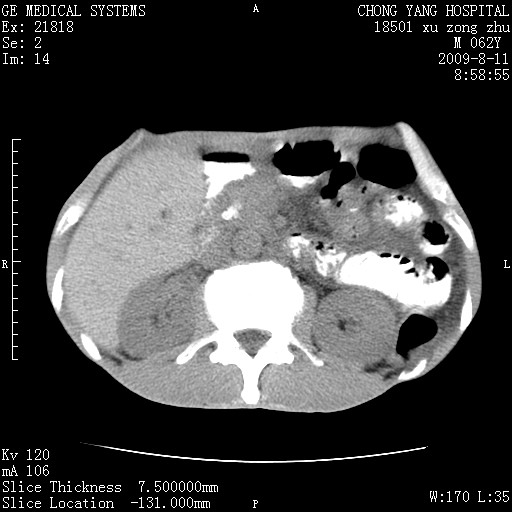

以下是引用杀毒软件在2009-8-11 16:35:00的发言:[br]肝内胆管扩张局限于左叶,胆管内有结石伴肝外胆管结石,胆管壁增厚呈弥漫性并发腹腔积液,胰腺边界模糊。[br][br]考虑---胆总管及肝内胆管结石继发胆管炎及胰腺炎,左肾下极囊肿,腹水。

以下是引用zjzjr在2009-8-11 17:35:00的发言:[br]肝内胆管扩张局限于左叶,胆管内有结石伴肝外胆管结石,胆管壁增厚呈弥漫性并发腹腔积液。[br][br]考虑---胆总管及肝内胆管结石继发胆管炎,左肾下极囊肿,腹水。